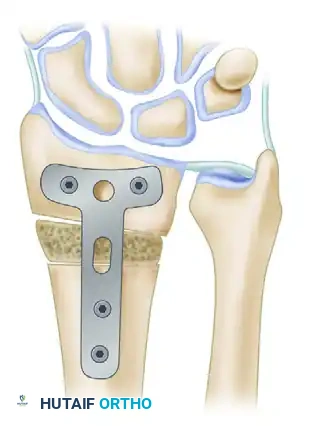

6. Internal Fixation

Stabilize the osteotomy and the intercalary graft using a robust volar plate. Historically, a 3.5-mm angled T-shaped plate was utilized, though modern anatomically contoured volar locking plates are now frequently employed.

7. Distal Radioulnar Joint (DRUJ) Assessment

Following rigid fixation of the radius, the tourniquet is deflated, and hemostasis is achieved. The DRUJ must now be dynamically assessed through a full range of pronation and supination.

If normal ulnar variance cannot be fully restored through the radial osteotomy alone, or if the DRUJ remains tight and incongruent, a concomitant ulnar shortening osteotomy must be performed to decompress the ulnocarpal joint and restore DRUJ kinematics.